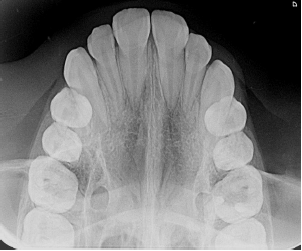

Qual a técnica radiográfica apresentada na imagem?

Provas